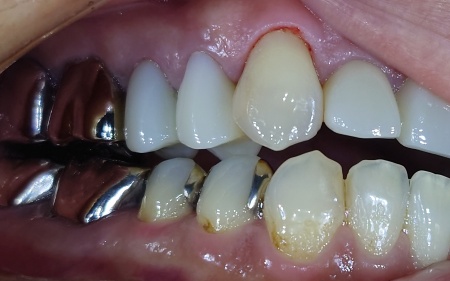

拝見したところ、右下の乳歯(第2乳臼歯)が抜けないまま、その下から永久歯が生え始めている「乳歯晩期残存」が認められました。

通常であれば乳歯は一定の時期に抜けますが、乳歯が残っているままだと永久歯が正しい位置に生えることができず、歯並びや噛み合わせに影響を及ぼす可能性があります。

また乳歯が残った状態では歯磨きがしにくくなり、汚れが溜まりやすいため、虫歯や歯周炎のリスクも高まります。

以上のことから、永久歯が正しい位置で生えるように促す必要があると診断しました。